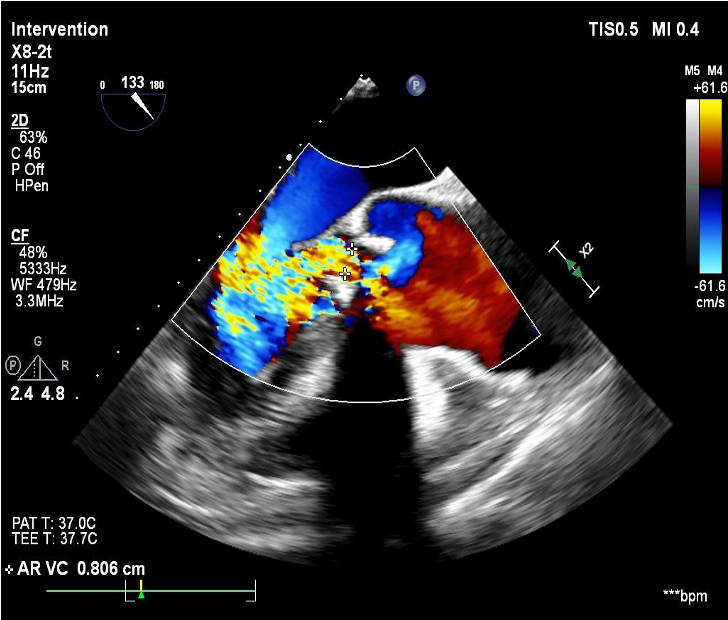

2D echo suggestive of severe aortic regurgitation. CT analysis done and we decided to opt for 24mm TAVR valve

SEV 24mm. was deployed and during reheathing patient developed circulatory collapse.